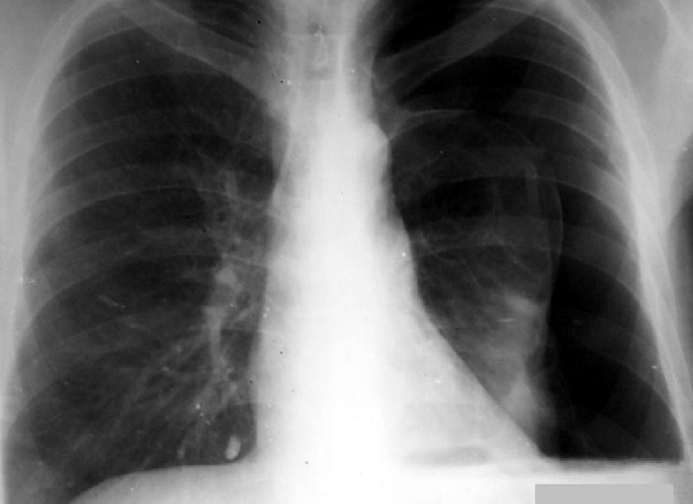

Произведено ультразвуковое исследование

(см. рисунок).

Опишите прилагаемую рентгенограмму.